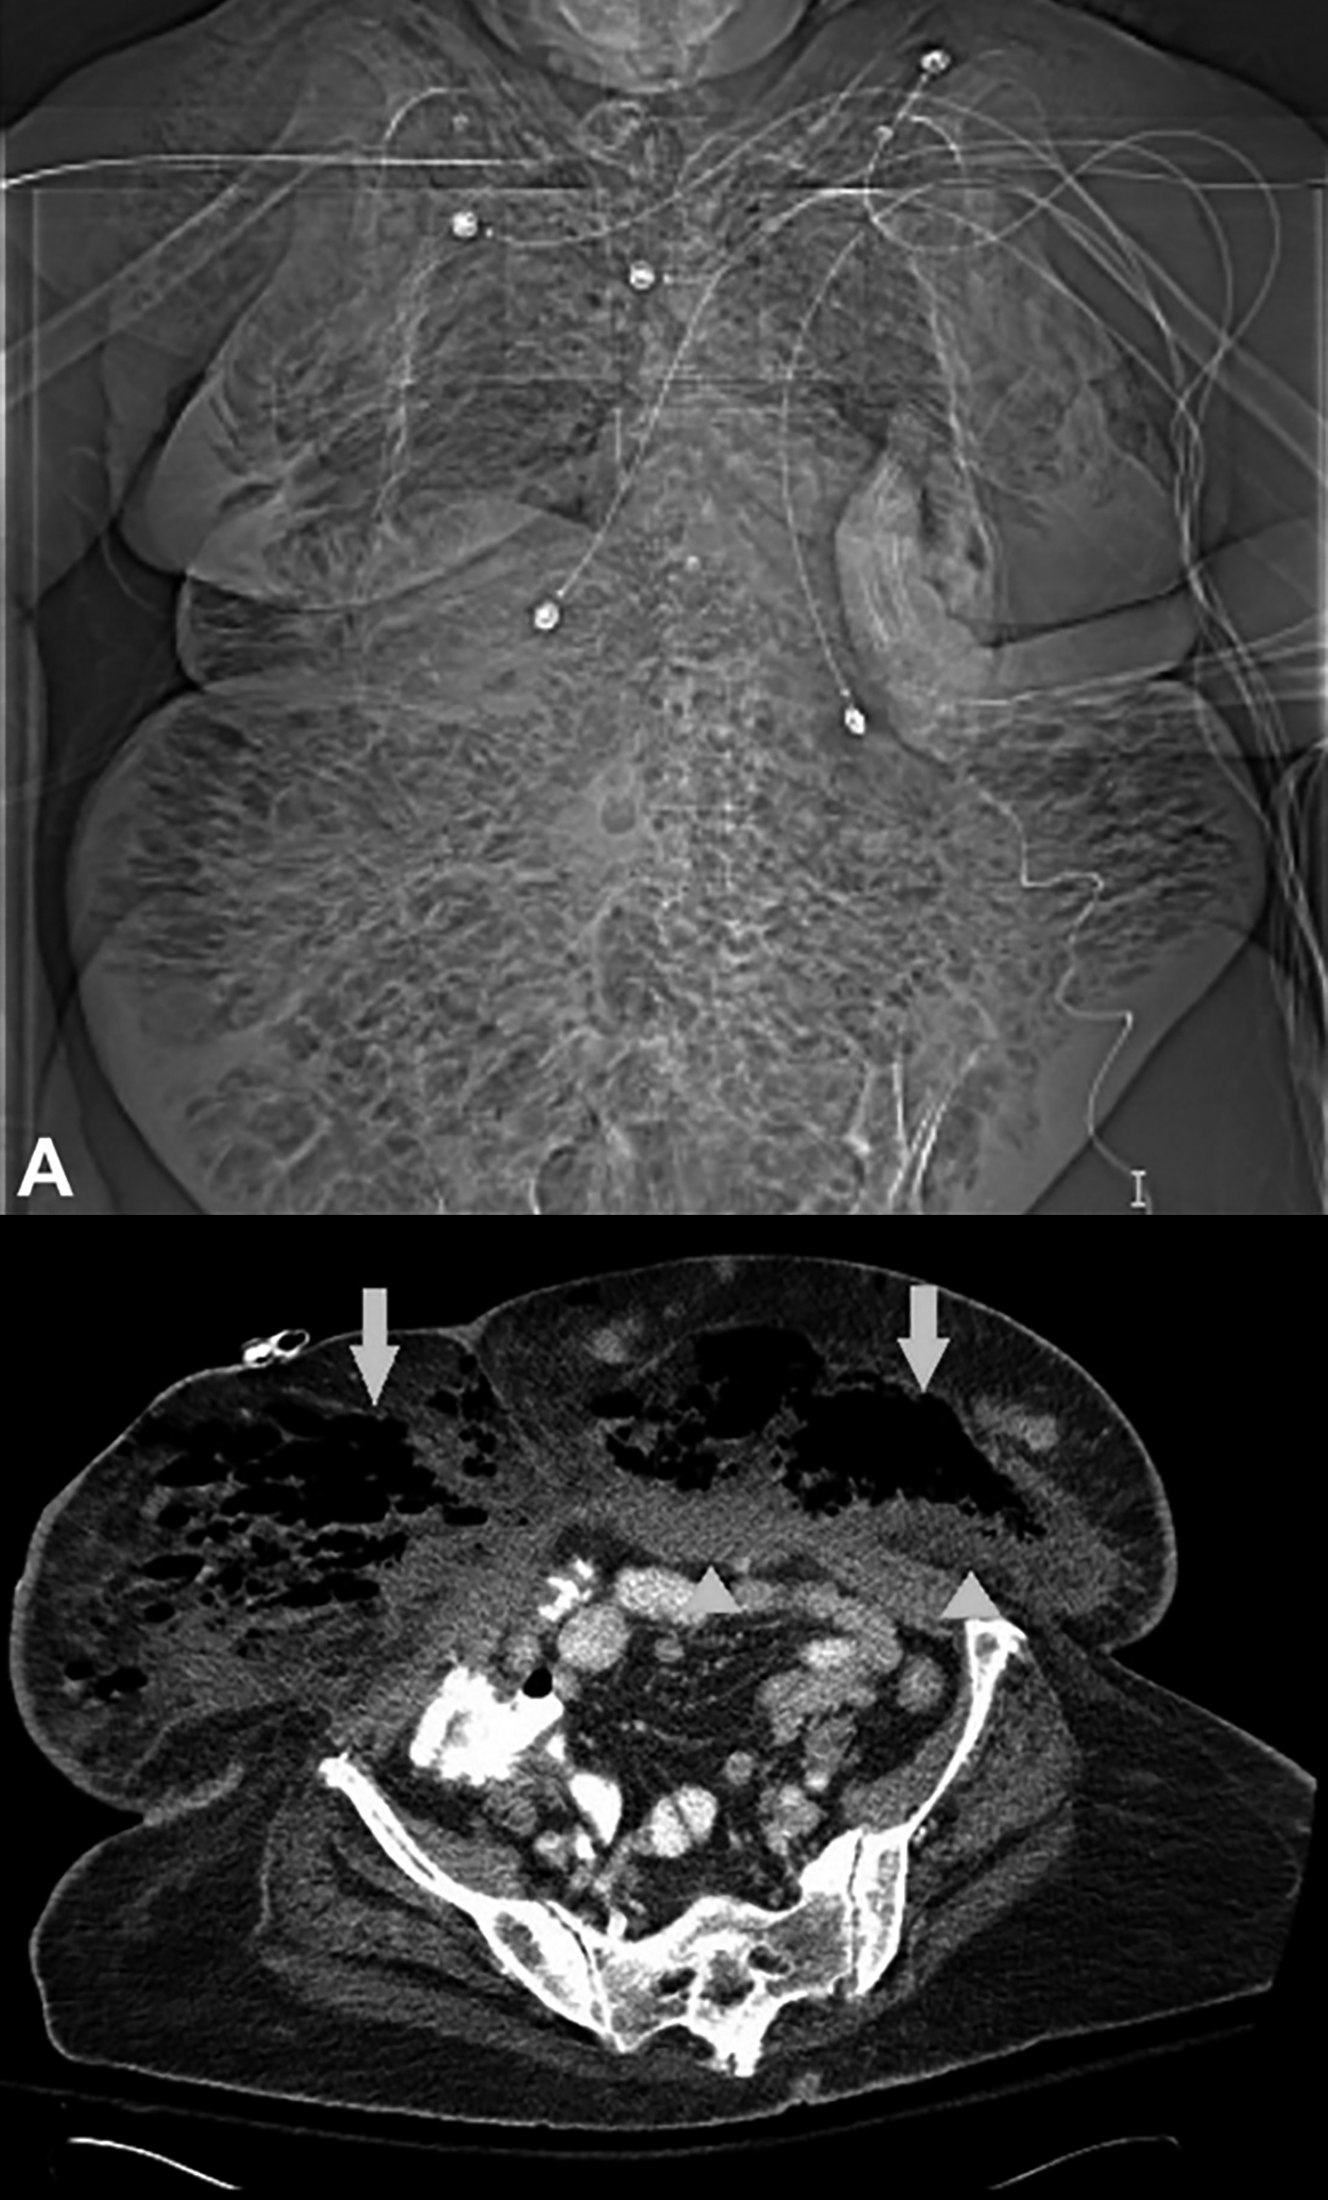

Figure 2: Computed tomography of the abdomen. (A) Scout film of computed tomography revealed subcutaneous emphysema throughout the abdominal wall and both breasts. (B) Axial sections of computed tomography demonstrating subcutaneous emphysema (arrows) and fat stranding (arrowheads) within the anterior abdominal wall.

An 81-year lady with a history of hypoxic encephalopathy (tracheostomy- and gastrostomy-dependent) and end-stage renal disease (ESRD) was brought to the emergency department (ED) with complaint of fever for 3 days. Upon evaluation, she was febrile, tachycardiac, and hypotensive. Subcutaneous emphysema was palpable throughout the abdomen and chest wall. Skin discoloration was also noted around the gastrostomy site (Figure 1). At the time of initial evaluation by ED physicians, the gastrostomy tube was noted to be dislodged. Of note, the gastrostomy tube was placed two years prior to the current presentation during a prolonged hospitalisation for septic shock. At that time, the patient required prolonged mechanical ventilation necessitating tracheostomy and gastrostomy. Since then, the patient had not experienced any gastrostomy-associated complications. In the ED, the gastroenterology team exchanged the tube at the bedside. She was resuscitated with intravenous fluids and started on clindamycin, meropenem, and vancomycin for broad-spectrum coverage. Initial laboratory investigations were remarkable for a total leukocyte count of 44,700/mm3 with 90% neutrophils. Abdominal computed tomography showed significant subcutaneous emphysema within the anterior abdominal wall and both breasts (Figure 2). These clinical features supported a diagnosis of abdominal wall-necrotising fasciitis. Her blood cultures grew Klebsiella pneumoniae (resistant to carbapenems) and polymyxin B (colistin) was added. The patient’s healthcare proxy was informed about the patient’s declining condition and the need for surgical debridement. In line with the patient’s previously stated wishes, surgical debridement was withheld and she eventually expired on the ninth day of admission.